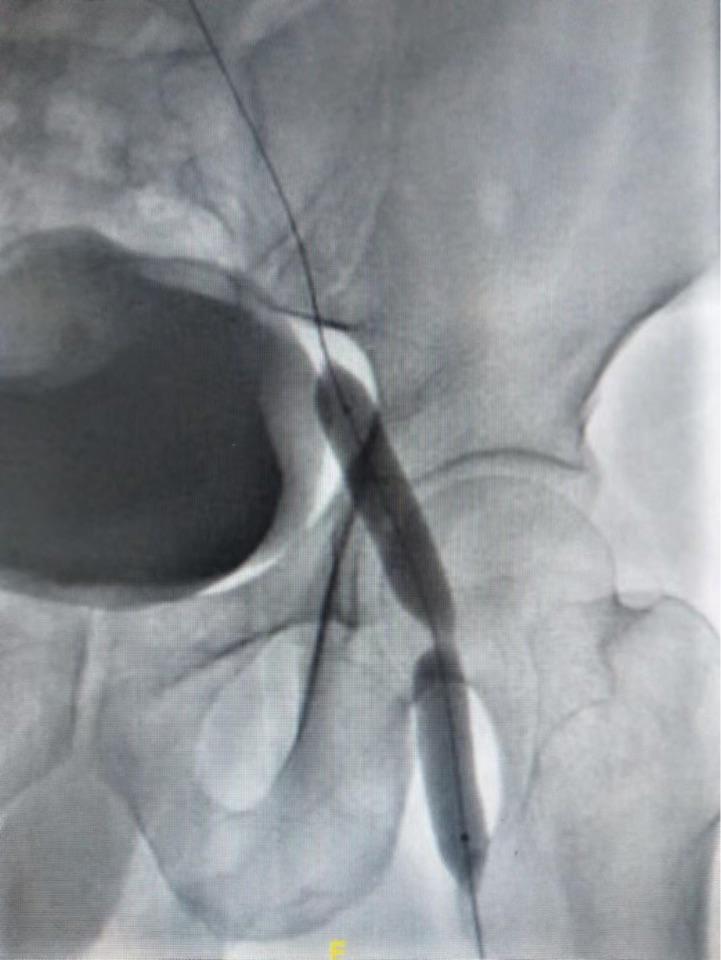

面对缝合后几乎完全闭塞的股静脉,开通、球扩、支架置入……结果满意!

最后造影,血流通畅,结果满意,患者症状改善。